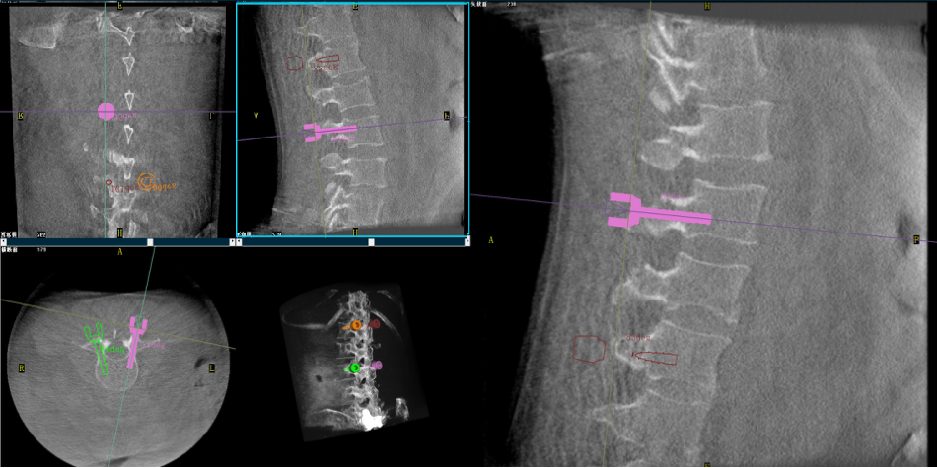

3. Планирование и навигация — определение траекторий винтов с возможностью их корректировки в реальном времени.

4. Роботизированное исполнение — установка направляющих игл и винтов под контролем робота.

5. Проверка результата — послеоперационный 3D-скан для подтверждения точности имплантации.

Случай 1 — Роботизированная ПВП

Пациентка: 60 лет

Диагноз: компрессионный перелом грудо-поясничного отдела, сколиоз

Преимущества робота:

• оптимальный угол пункции

• больший объём введения цемента

• меньшее количество флюороскопии

• идеальная траектория входа

Результат:

Стабильная фиксация, низкий риск повторного перелома, быстрое восстановление.